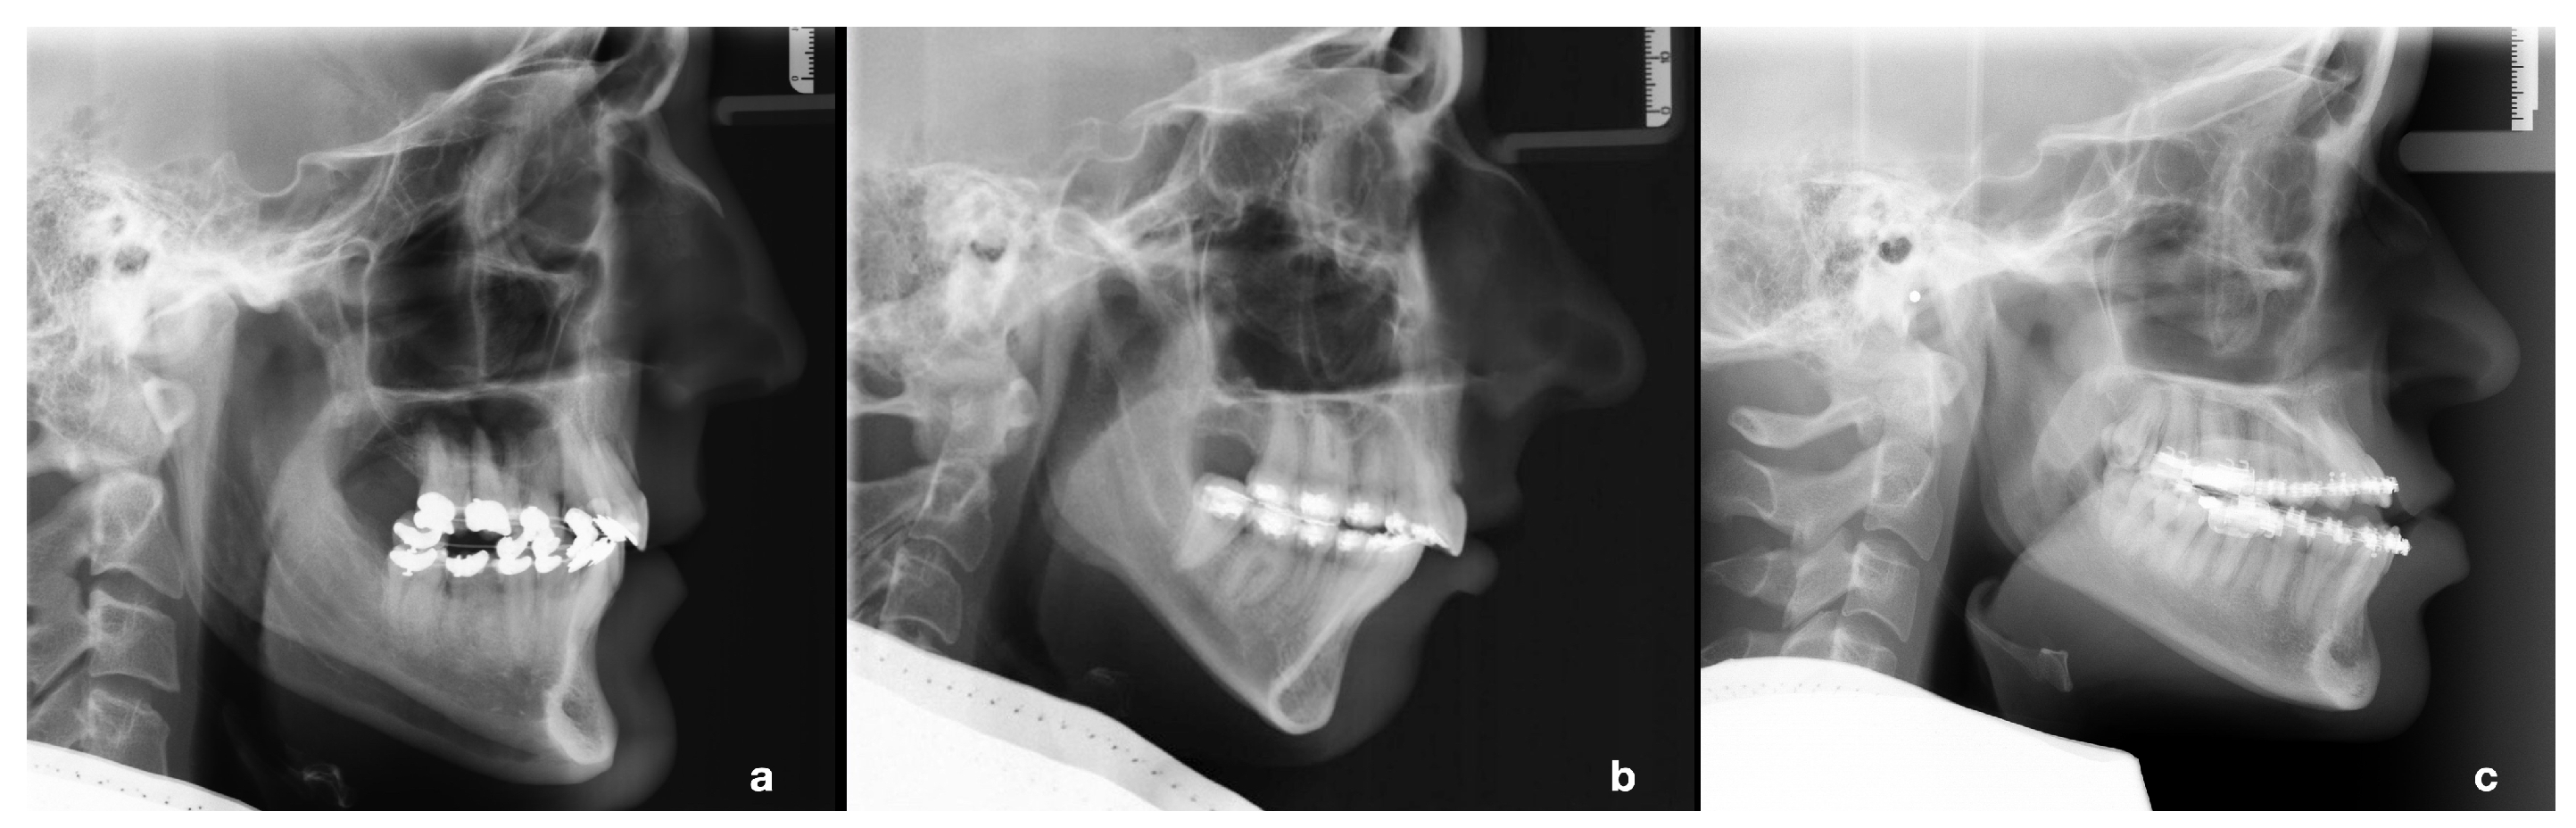

| age | 128 | 28.1 | 9.1 | 204 | 26.2 | 7.8 | 182 | 26.5 | 9.0 | n. s. | |

| female | 36 | 26.3 | 9.2 | 171 | 26.0 | 7.9 | 116 | 26.3 | 9.7 | n. s. | |

| male | 92 | 28.8 | 9.0 | 33 | 27.6 | 7.0 | 66 | 26.9 | 7.9 | n. s. | |

| 128 | 7.8 | 3.4 | 204 | 11.1 | 3.3 | 182 | 2.4 | 4.0 | <0.001 | ||

| AxV | 128 | 36.2 | 4.6 | 204 | 26.5 | 3.8 | 182 | 35.9 | 4.5 | <0.001 1 | |

| AxH | 128 | 98.9 | 5.5 | 204 | 88.1 | 5.4 | 182 | 85.6 | 5.6 | <0.001 | |